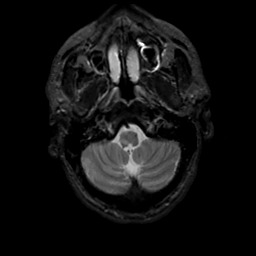

MR Study #13, May 19, 1991 -- Slice #6